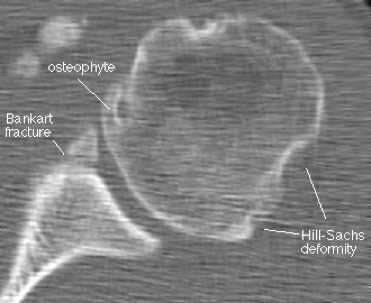

На КТ хорошо видны костные дефекты и дефекты гиалинового хряща суставной впадины. Гиалиновый хрящ, покрывающий головку плечевой кости виден гораздо хуже.

КТ плечевого сустава, Переломы Банкарта и Хилла-Сакса.

• Костный перелом Банкарта: костно-хрящевой перелом передненижнего отдела суставной впадины лопатки

• Перелом Хилла-Сакса: костно-хрящевой импрессионный перелом задневерхнего отдела головки плечевой кости

о Передний вывих: переломы Хилла-Сакса и Банкарта

о Задний вывих: обратные переломы Хилла-Сакса или Банкарта